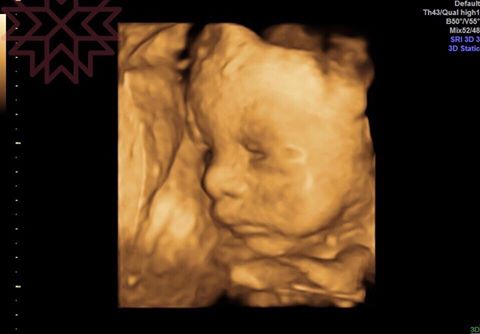

~你看

這眼皮不是張開了嗎⋯⋯

根據研究

平均胎兒要到妊娠26到28周以後

才會觀察到有張眼跟眨眼的動作

而一般要32周以後

才隱約可以辨認物體的形狀